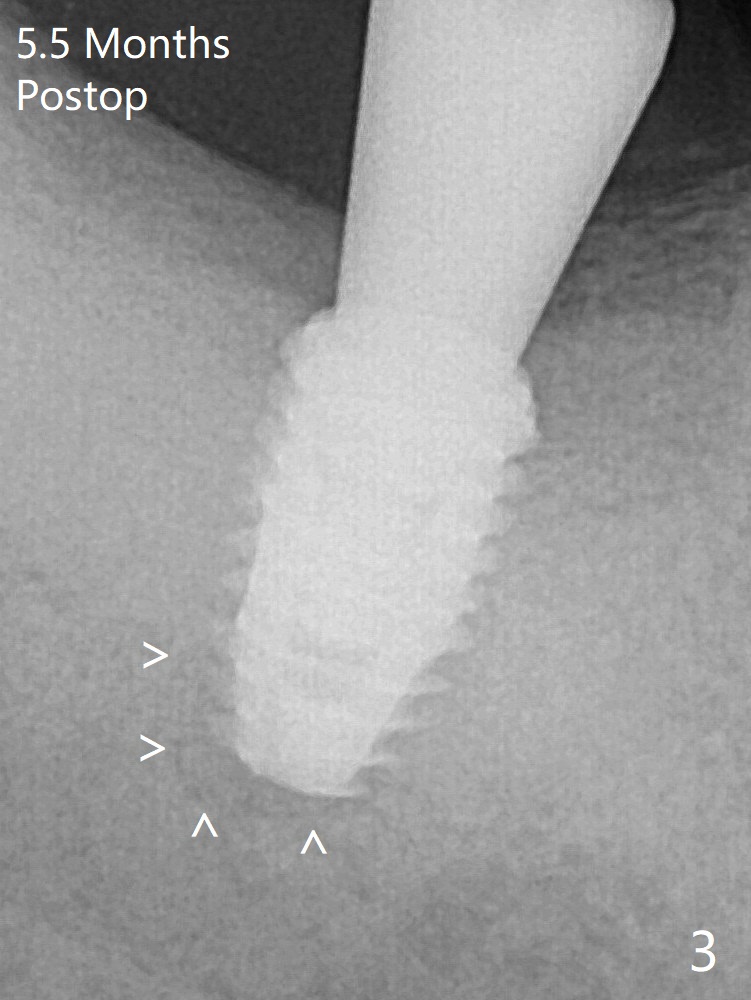

A 5x8.5 mm implant achieved primary stability in the final 1-2 mm. The implant was then placed ~ .5 mm deeper (~ 40 Ncm) (Fig.1). The implant, apparently having been osteointegrated 5.5 months postop (Fig.3), was placed deep, probably related to pressing the distal end of the guide too heavily. It is difficult to restore with use of a 5.2x5.5(5) mm abutment. There is apical bone loss (arrowheads), most likely due to the dense bone and heat during osteotomy.